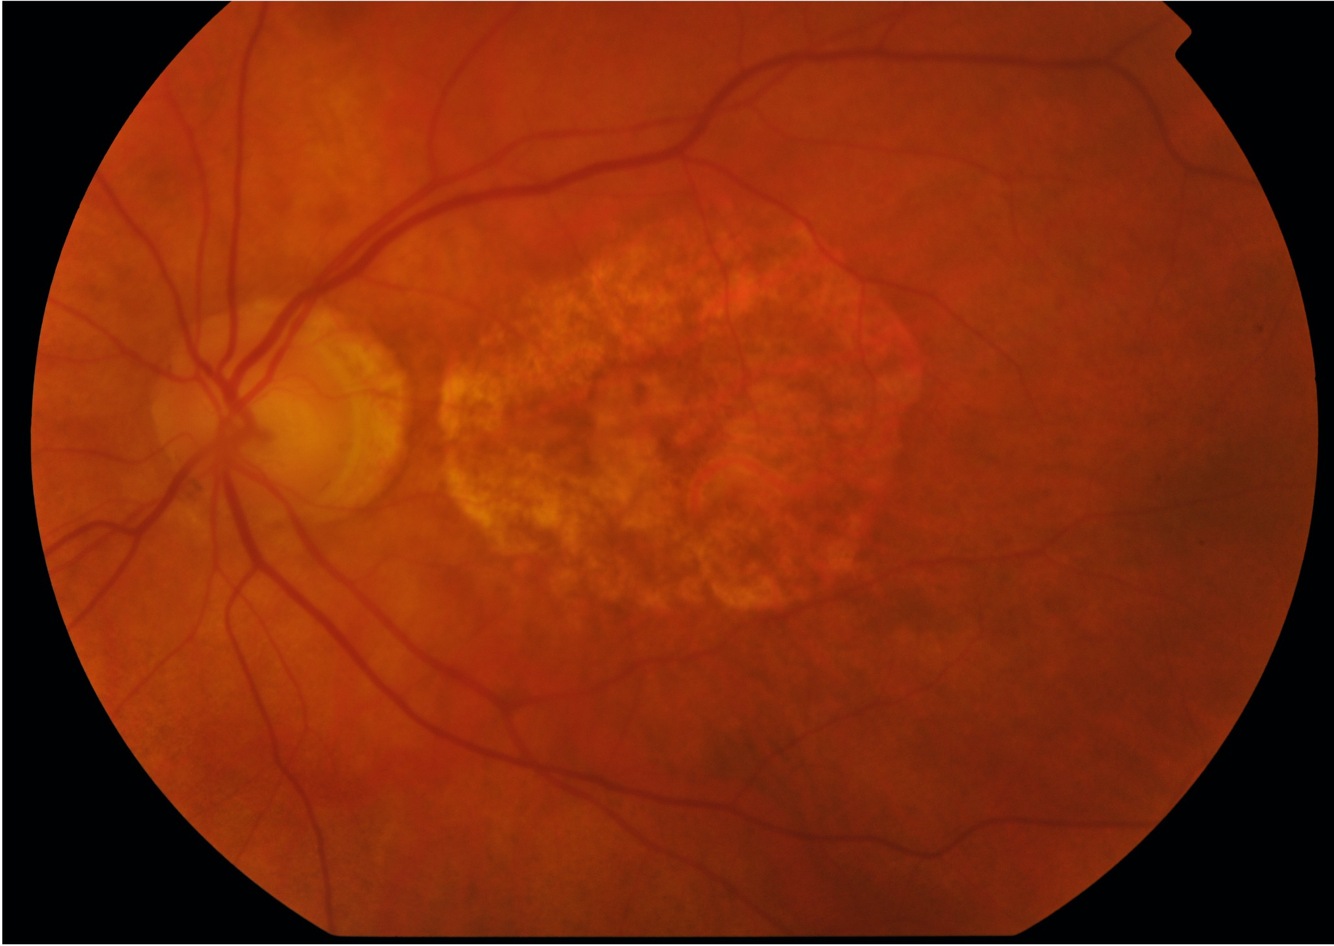

20

• Neovascular membrane

• Haemorrhage